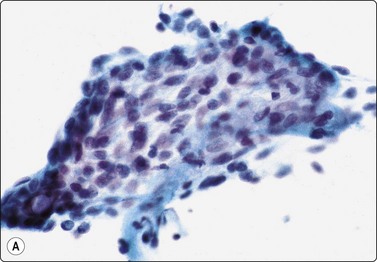

Benign lymphoepithelial lesion/myoepithelial sialadenitis

Benign lymphoepithelial lesions are swellings of salivary glands caused by a reactive lymphoid infiltrate with follicular hyperplasia, which obliterates the acinar glandular tissue and causes proliferation and disruption of ductal epithelium. It may clinically manifest as Sjögren’s syndrome. Smears from a benign lymphoepithelial lesion are characterized by small clusters of ductal epithelial cells associated with lymphocytes and with a background of lymphoid cells (Fig. 4.28). The smear pattern is reminiscent of autoimmune thyroiditis. The condition is associated with HIV infection.97

image

Fig. 4.28 Benign lymphoepithelial lesion

Aggregate of ductal epithelial cells associated with many lymphoid cells (Pap, HP).

The most important differential diagnosis is lymphoma, mainly MALT lymphoma. This often requires immunological studies, most conveniently by flow cytometry of aspirated material. Branchial cyst in which only the lymphoid component has been sampled should also be considered.